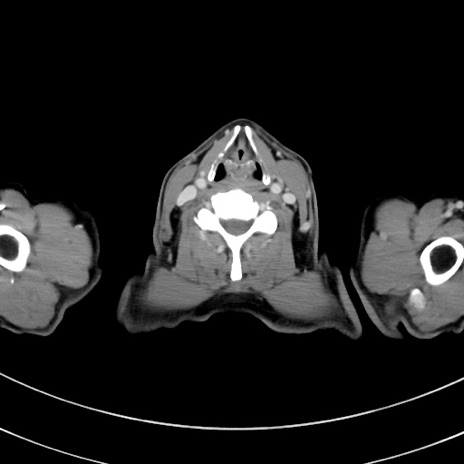

冠状断像

【症例】 60歳代男性

【主訴】 黒色吐物

【現病歴】 4日前から嘔気自覚、2日前の朝食後にも嘔気あり、自分で手で嘔吐反射起こし嘔吐したところ血が混ざっていたため受診。

【既往歴】 5年前汎発性腹膜炎を伴う急性虫垂炎で手術、高血圧、前立腺肥大症、高脂血症

【身体所見】 腹部正中に手術癩痕あり 腹部平坦・軟圧痛なし膨満感あり

【データ】WBC 8400、CRP 4.54